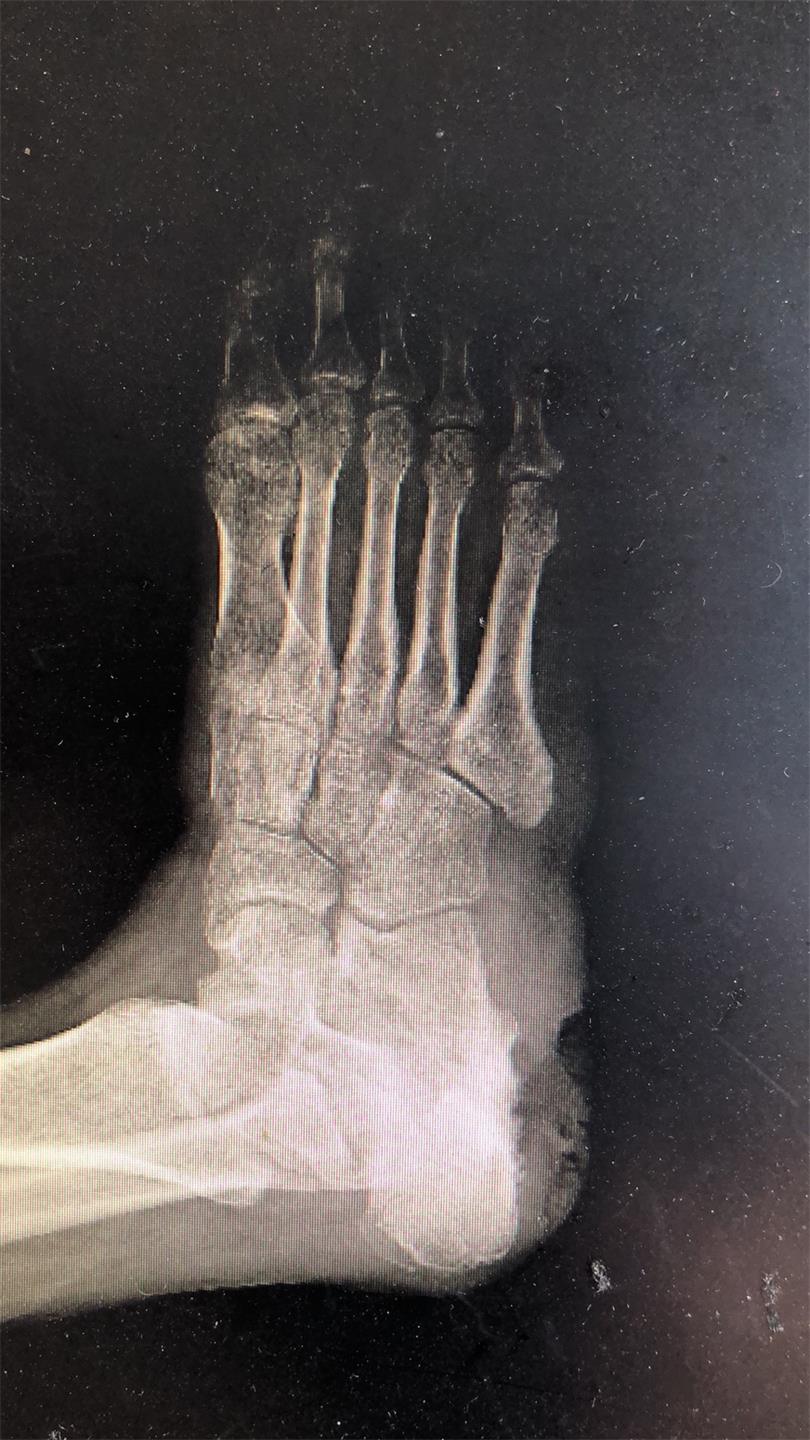

经检查,叶大伯的右踝部明显红肿,足跟的皮肤组织呈暗灰色,还有不少暗灰色的“脓水”渗出,内踝下有一条约1cm长的窦道,并且有不少淡黄色液体渗出。叶大伯的右足跟皮肤坏死、右足跟慢性骨髓炎伴软组织感染至右足疼痛畸形,时间长达30余年。